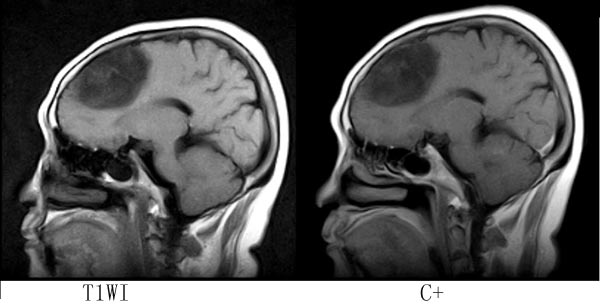

女,64岁,ct示右侧额叶占位,平扫无钙化,增强无强化,mr平扫+增强,请大家诊断.

病灶位于右额叶,呈不均匀长t1长t2信号,部分液化,占位效应不明显,无强化,临近颅板无受侵,考虑分化程度较高的胶质瘤。

考虑星形细胞瘤 诊断依据:TIW低信号 T2W高信号 瘤体靠近皮层下,周围是个囊腔(“囊在瘤内”),瘤体强化不明显,部分跨越中线,浸润及占位效应不明显,愈后较好。